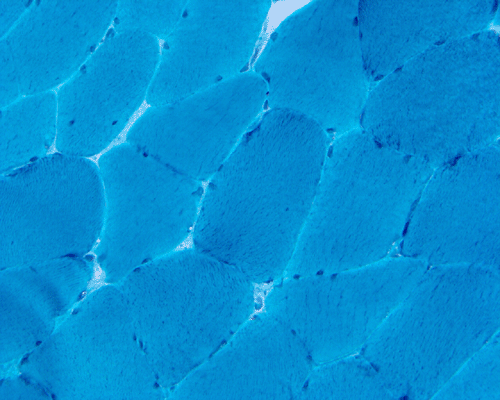

Hematoxylin and eosin stained sections do not show significant abnormal findings. There was no necrotic fibers or regenerating activity, no inflammatory cell infiltration or evidence of vasculitis (Panel A). The modified Gomori's trichrome stain  (Panel B) shows a minute amount of subsarcolemmal deposition which would be normal in this age group. There is no remarkable findings in the ATPase  (Panel C), NADH-TR  (Panel D), succinate dehydrogenase  (Panel E), cytochrome c oxidase  (Panel F), and esterase  (Panel G). There is some reduction in PAS staining (Panel H). The PAS staining with diastase digestion (Panel I) is within normal limits. The phosphorylase reaction is within normal limits (Panel J). The adenylase deaminase preparation is entirely negative (Panel K) in comparison to the positive controls (Panel L); the reaction is repeated and the same result is obtained.

Pathology: MADD does not lead to morphological changes per se. Adenylate deaminase can be easily demonstrated by histochemistry on frozen sections. The reaction is a tetrazolium-based reaction and the reactive product is blue. Biochemical analysis can confirm the deficiency and the isoform. The truncated protein cannot be demonstrated by immunofluoresence.